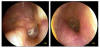

JFC otopatía supurativa crónica inactiva (der) y con colesteatoma atical (izq)